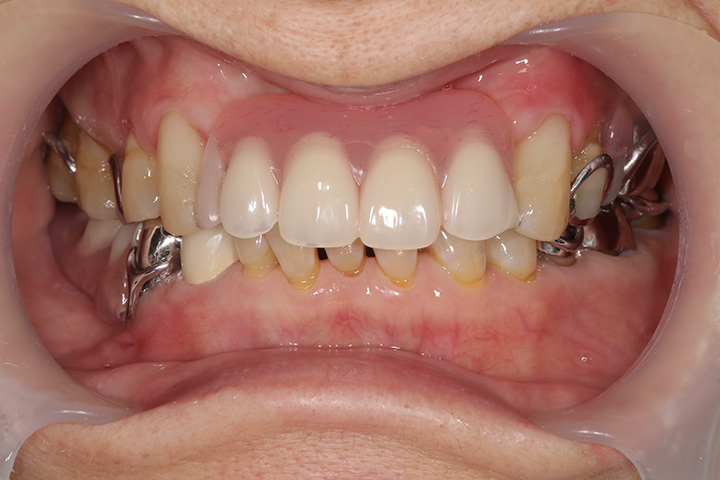

部分入れ歯は人工の歯だけだと落ちてくる、動くという現象が起こるため、上の写真のようにクラスプという細い金属を残っている歯にかけることになります。

こちらの写真は部分入れ歯を装着したところですが、クラスプ(残っている歯にかかっている細い金属)が確認できます。